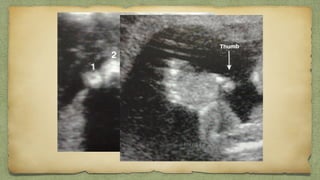

LIMB

S๏ฑ Confirm the 3 long bones

๏ฑ Presence of Foot & Hand

๏ฑ Complete Absent....Amelia

๏ฑ Look for Phacomelia

Phacomelia

๏ฑBone scanned throughout long section

๏ฑLook for any bowing ,angulation ,#

๏ฑClub foot

๏ฑNo of fingers